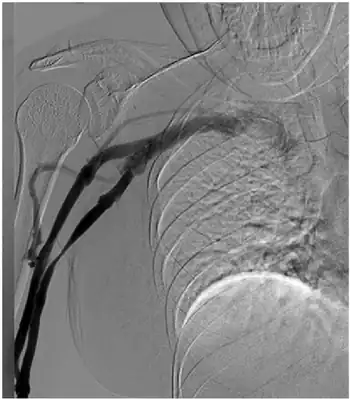

| Findings consistent with pectoralis minor syndrome on the right side | |